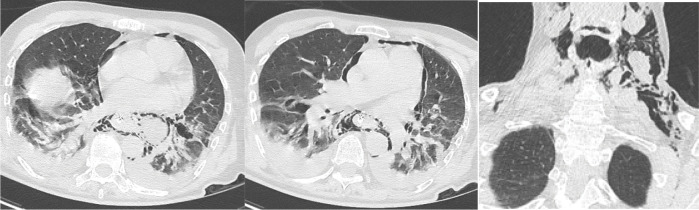

本文报告一位70岁女性患者,长期以进食困难伴固体食物为主诉,报告Boerhaave综合征。她腹痛24小时,伴有恶心和粪便性呕吐。患者有呼吸急促、心动过速、缺氧、腹部守卫、无肠音。胸腹计算机断层扫描显示幽门壁明显增厚,伴有继发性胃膨胀、颈部皮下肺气肿、双侧胸腔积液和纵隔气肿。

A case is presented of Boerhaave syndrome in a 70‑year‑old female patient complaining of dysphagia with solids for a long time. She consulted for abdominal pain for 24 hours, accompanied by nausea and fecal vomiting. The patient had tachypnea, tachycardia, hypoxia, abdominal guarding, and absence of bowel sounds. Thoracoabdominal computed tomography revealed significant pyloric wall thickening with secondary gastric distension, cervical subcutaneous emphysema, bilateral pleural effusion, and pneumomediastinum.